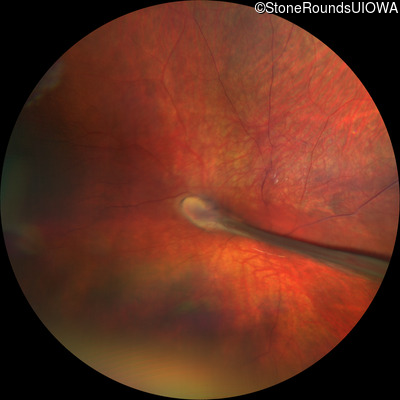

AD Familial Exudative Vitreoretinopathy (IIIE2b)

Age at visit: 23 months

This 23 month old male has had nystagmus since shortly after birth. He was born at term (7lbs 12oz).